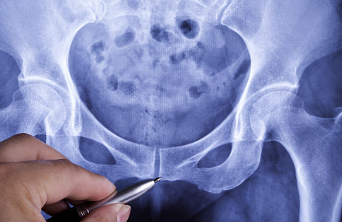

꼬리뼈는 인간의 척추뼈 구조 중 하나로, 척추 열의 맨 아래쪽에 위치합니다. 꼬리뼈은 척추의 일부이지만, 현대인들은 더 이상 꼬리를 갖고 있지 않으므로 기능을 하지 않습니다. 하지만 꼬리뼈는 인간의 진화적 역사에서 중요한 역할을 했었습니다. 리뼈는 뼈 자체로는 작지만, 다리와 척추를 연결하고 균형을 잡는 역할을 하며, 혹은 충격을 흡수하여 상해를 예방하는 역할을 합니다.

꼬리뼈 부근 통증은 다양한 원인에 의해 발생할 수 있습니다. 일반적으로 꼬리뼈 자체에 직접적인 문제가 있는 것은 드뭅니다. 대부분의 경우 꼬리뼈 주변 조직에 문제가 생긴 것이 원인입니다.

또한 뼈 조직이 아닌 주변 조직인 인대, 근육, 신경 등에 문제가 생긴 경우에도 꼬리뼈 부근 통증이 발생할 수 있습니다. 척추 디스크의 이상으로 인해 디스크가 꼬리뼈 부근으로 압박되면 인대와 근육에 긴장이 생겨 통증을 유발합니다. 또한 꼬리뼈 부근을 관통하는 신경이 염증을 일으키거나 압박을 받으면 통증이 나타납니다.

또한 근골격계 질환으로 인해 꼬리뼈 부근 통증이 나타날 수 있습니다. 척추측만증, 척추관협착증 등의 질환으로 인해 척추의 구조가 변형되면서 꼬리뼈 부근에 압력이 생기고, 이로 인해 통증이 발생할 수 있습니다.